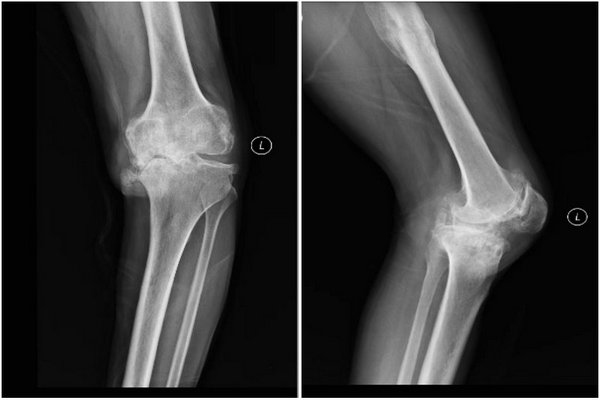

术前影像